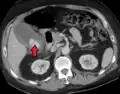

Acute cholecystitis with gallbladder wall thickening, a large gallstone, and a large gallbladder -

Right upper quadrant abdominal ultrasound is most commonly used to diagnose cholecystitis.[1][26][27] Ultrasound findings suggestive of acute cholecystitis include gallstones, pericholecystic fluid (fluid surrounding the gallbladder), gallbladder wall thickening (wall thickness over 3 mm),[28] dilation of the bile duct, and sonographic Murphy's sign.[13] Given its higher sensitivity, hepatic iminodiacetic acid (HIDA) scan can be used if ultrasound is not diagnostic.[13][14] CT scan may also be used if complications such as perforation or gangrene are suspected.[14]